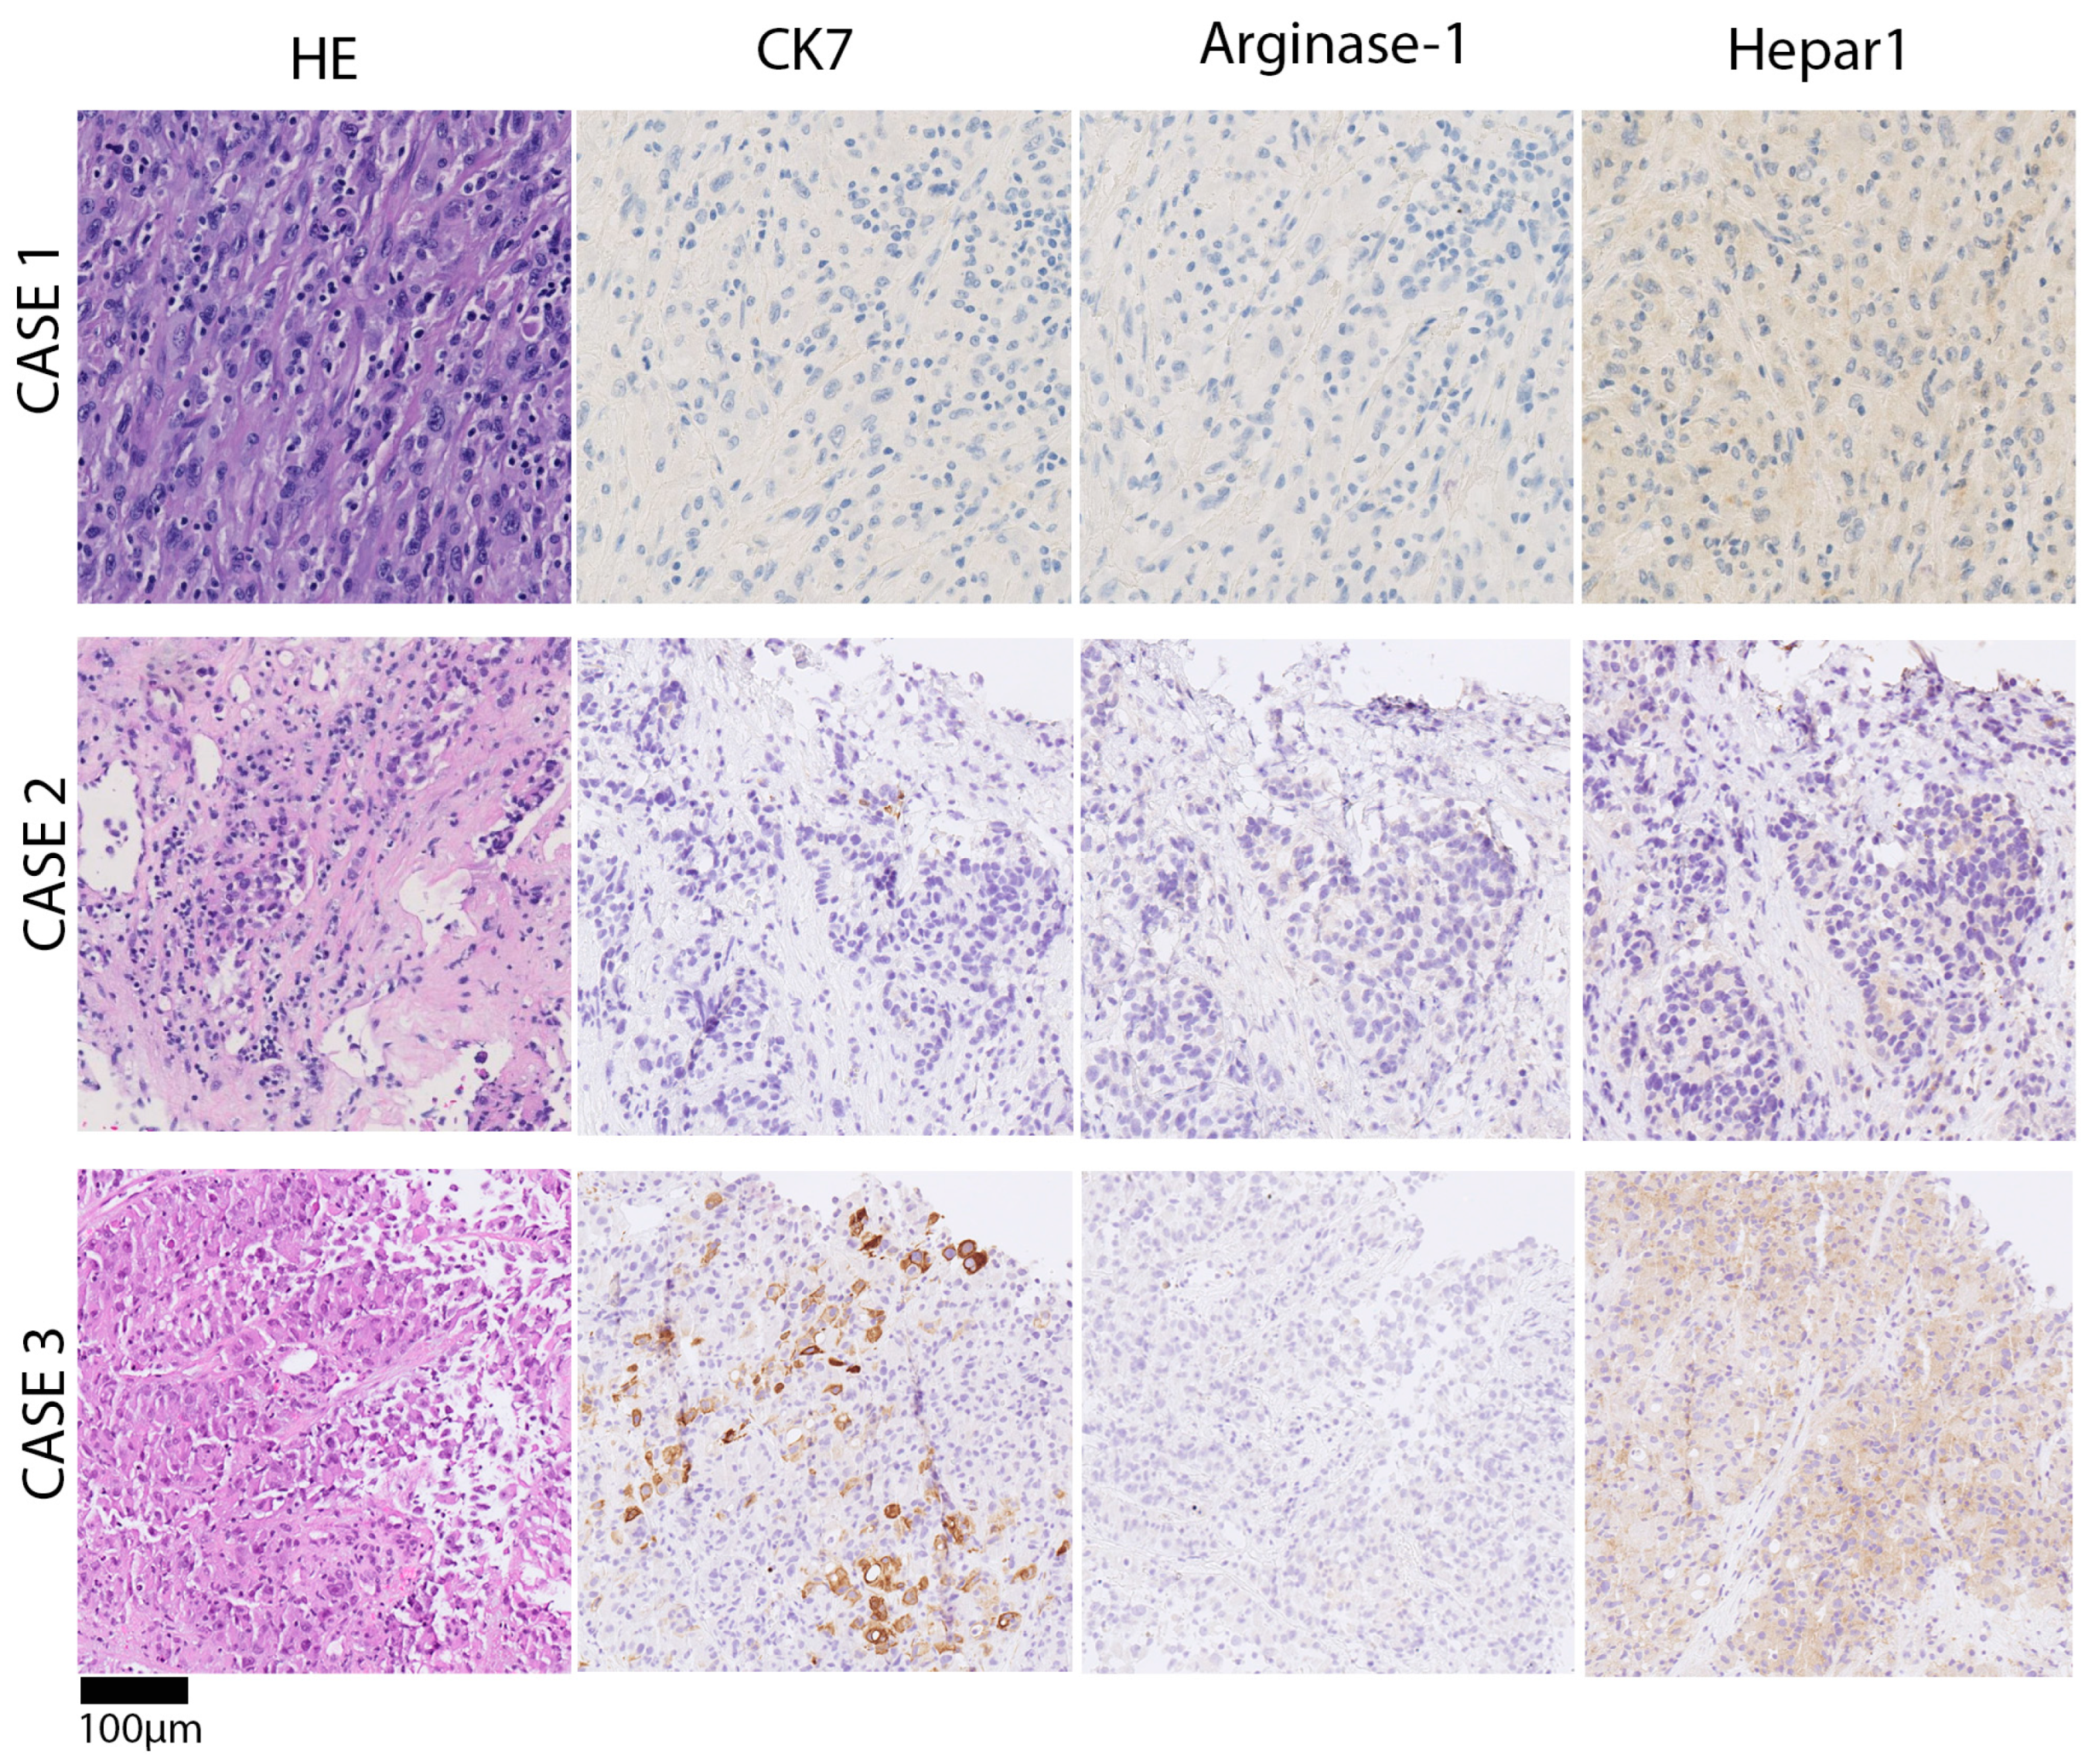

2. Materials and Methods

3. Results